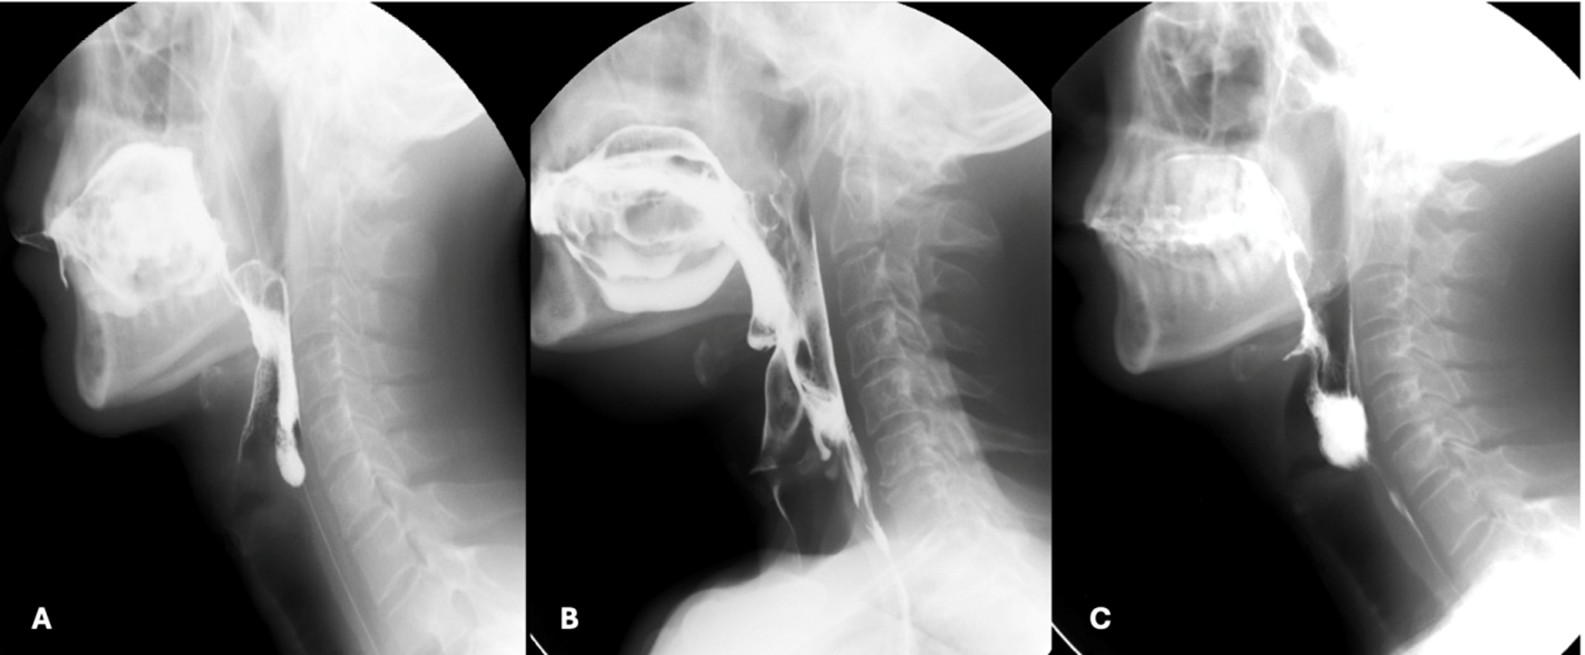

The preparatory phase of deglutition applies exclusively to the deglutition of solid food and boluses are prepared through a three-stage process that occurs simultaneously17: phase I transport - the tongue performs rotational movements to displace food posteriorly and laterally onto the occlusal surface of postcanine teeth; food processing - mastication and mixture of food with saliva alters the consistency of the boluses and prime it for swallowing; and phase II transport - processed food is pushed to the oropharynx, where it aggregates before being swallowed. By combining clinical and radiological evaluations, defects such as prolonged food processing time or reduced tongue movements can be identified. (Fig. 3)

Figure 3: Preparatory phase of a solid bolus shows mastication (A) followed by phase II transport to the oropharynx (B and C) before swallowing (D)